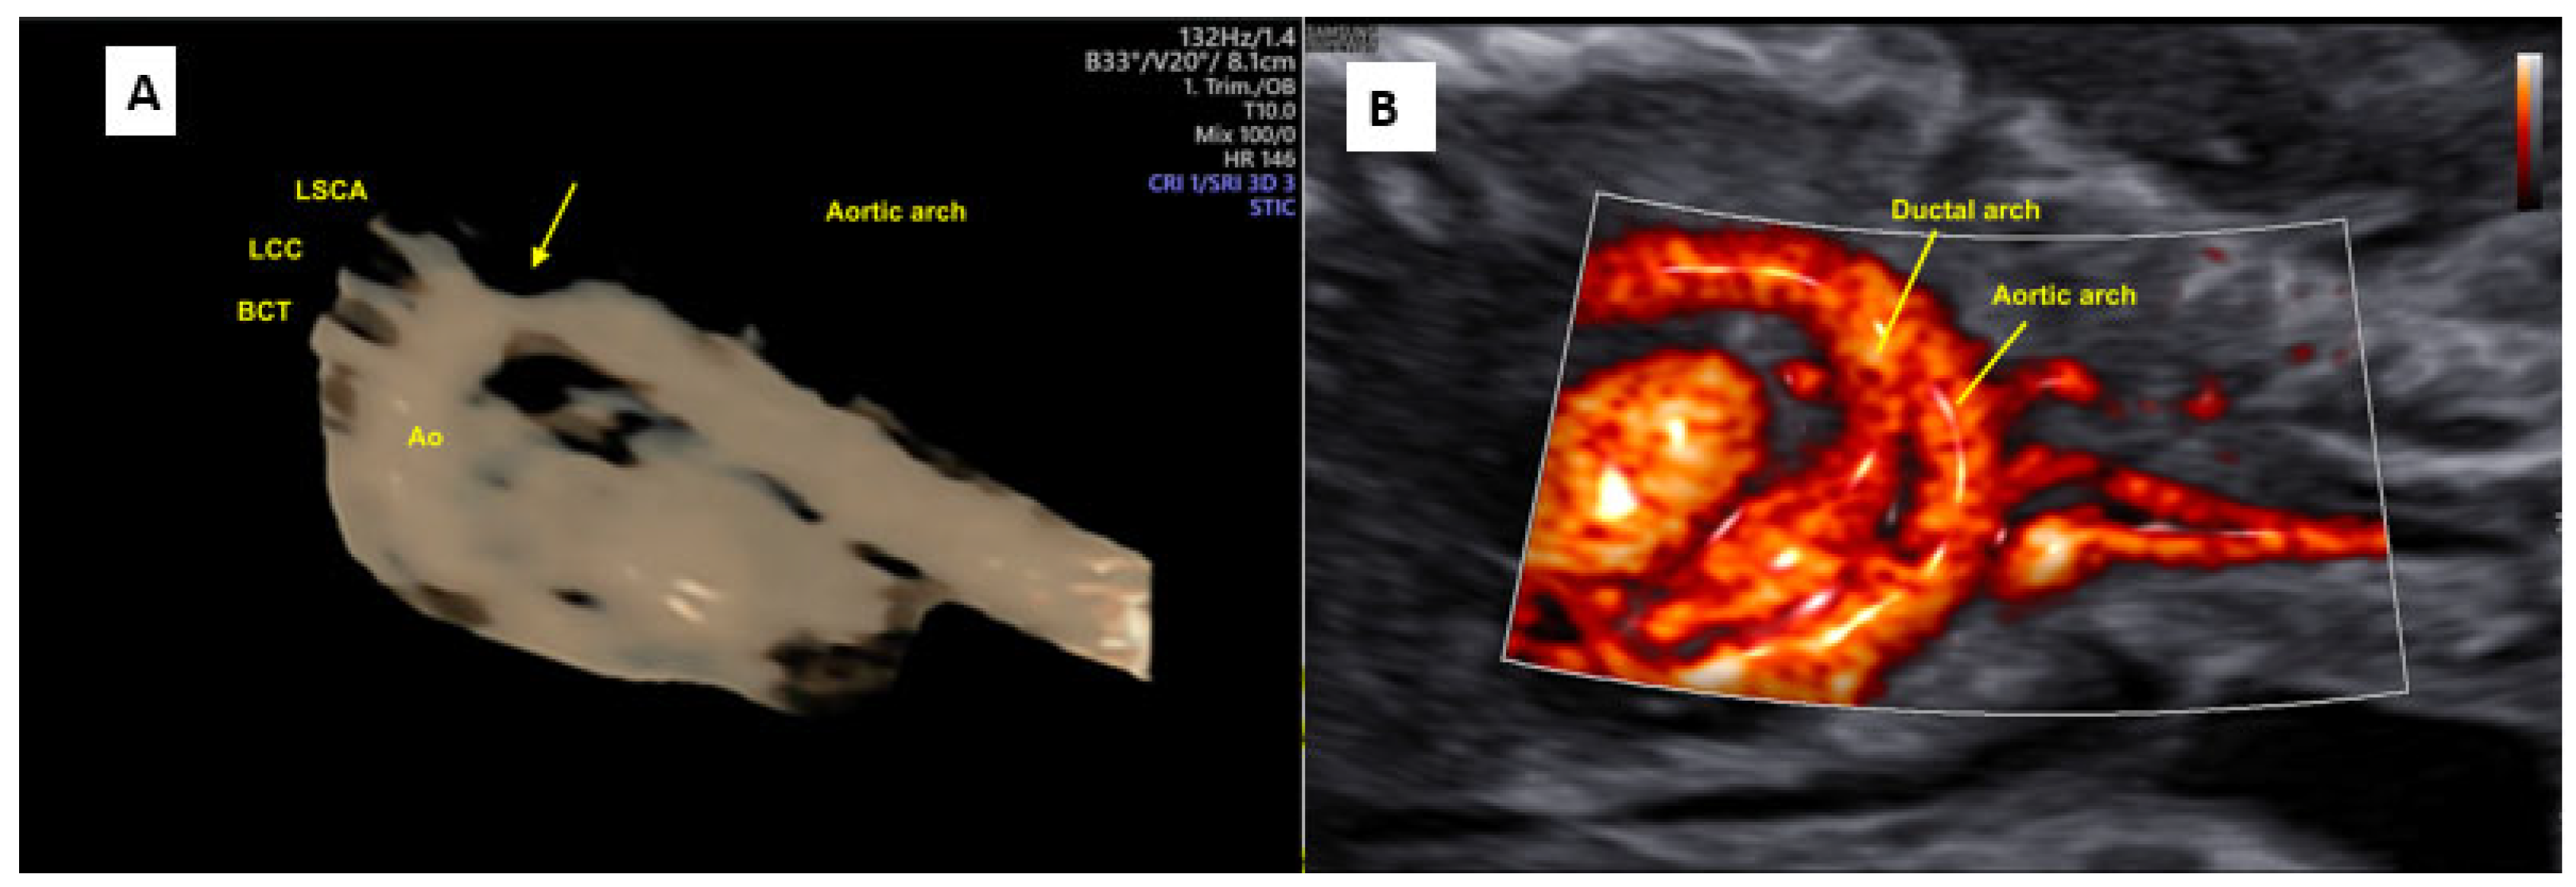

- Yeo L, Romero R, Jodicke C, Kim SK, Gonzalez JM, Oggè G; et al. Simple targeted arterial rendering (STAR) technique: A novel and simple method to visualize the fetal cardiac outflow tracts. Ultrasound Obstet Gynecol 2011, 37, 549–556.

- Araujo Júnior E, Tonni G, Bravo-Valenzuela NJ, Da Silva Costa F, Meagher S. Assessment of Fetal Congenital Heart Diseases by 4-Dimensional Ultrasound Using Spatiotemporal Image Correlation: Pictorial Review. Ultrasound Q. 2018, 34, 11–17.

- Zhang S, Wang N, Qu P, Shu X, Mi Y, Gao X. Prenatal echocardiography diagnosis of a novel combination of bilateral ductus arteriosus and cardiovascular anomalies: A case report and literature review. Front Cardiovasc Med. 2024, 11, 1389759.

- Lloyd DFA, van Poppel MPM, Pushparajah K, Vigneswaran TV, Zidere V, Steinweg J; et al. Analysis of 3-Dimensional Arch Anatomy, Vascular Flow, and Postnatal Outcome in Cases of Suspected Coarctation of the Aorta Using Fetal Cardiac Magnetic Resonance Imaging. Circ Cardiovasc Imaging. 2021, 14, e012411.